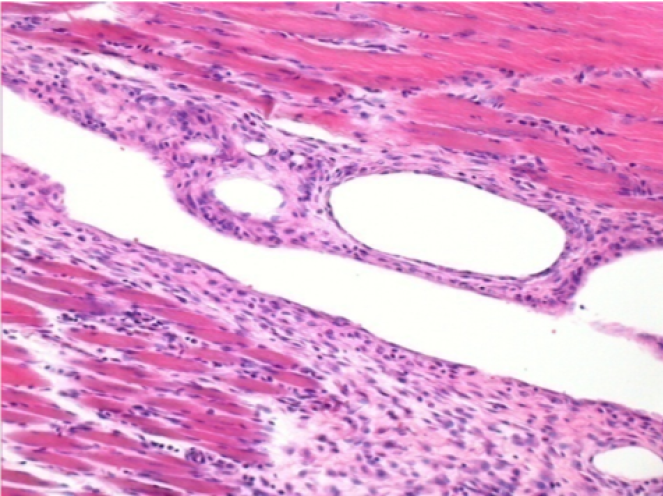

1 mes después de la inyección de Endopeel 0,1 ml en el músculo pretibial derecho.

¡Lo que se ve en negro en las imágenes no es una necrosis como podrían imaginar algunos científicos!

De hecho, hay que tener en cuenta 4 conclusiones